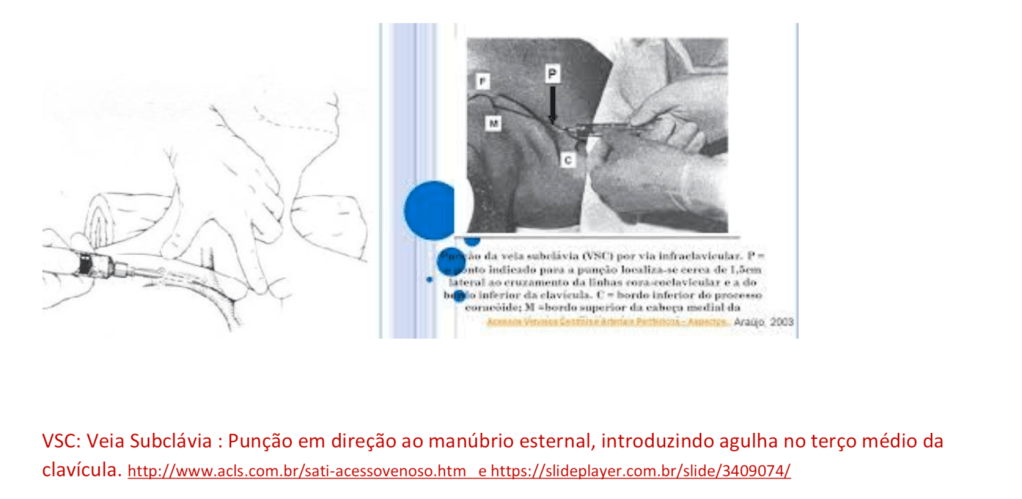

à artéria e ao plexo braquial. Temos tecnicamente duas opções de punção da veia subclávia que no caso são infraclavicular e supraclavicular.

ACESSO INFRACLAVICULAR:

• Colocar paciente em posição de Tredelemburg, girar cabeça para o lado contra-lateral a punção,

posicionar um coxim sob os ombros.

• Escolher local de punção, embaixo e discretamente medial ao ponto médio da clavícula.

• Introduzir agulha do cateter 2 cm abaixo da clavícula, utilizar seringa de 10 ml.

Avançar agulha lentamente e com discreta aspiração, orientada para fúrcula esternal e paralela a parede torácica, até que ocorra refluxo de sangue, desconectar seringa e progredir cateter.